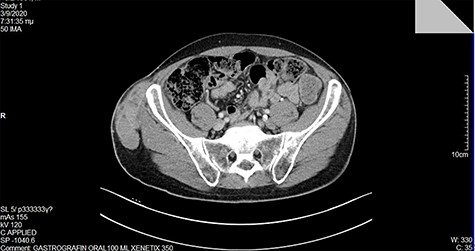

At our institution, on clinical examination, surgeons verified the swelling of the ilioinguinal aera and detected at tumescent, palpable and hard mass of the right pelvic fossa (Fig. 3). Lab examinations were unremarkable. Subsequent pelvic magnetic resonance imaging (MRI) (Fig. 4) and computed tomography (CT) scan identified a tumescent lipomatous tumor, without the presence of any metastatic lesions. Guided biopsy indicated the presence of an ilioinguinal liposarcoma located into the fatty tissue of the right iliac fossa. Following these, the interdisciplinary team decided to schedule a primary complete curative resection of the tumor (R0).

During the operation, surgeons exposed meticulously the liposarcoma that was utterly removed, and performed elective resection of the right iliac crest, the upper part of the sartorius muscle, part of the gluteus maximus muscle, and part of the muscles of the anterior abdominal wall in order to eliminate the potentiality of local recurrence of the liposarcoma (Figs. 5–7). The operation was uneventful, and two drainages were placed into the pelvic fossa. The drainages were removed the sixth postoperative day when the patient was finally discharged with instructions. The pathology report documented a well-differentiated liposarcoma of the right pelvic fossa. Finally, at the 6-month follow-up, the patient had no complication or recurrent lesions and oncologists declared that adjuvant therapy was not essential.